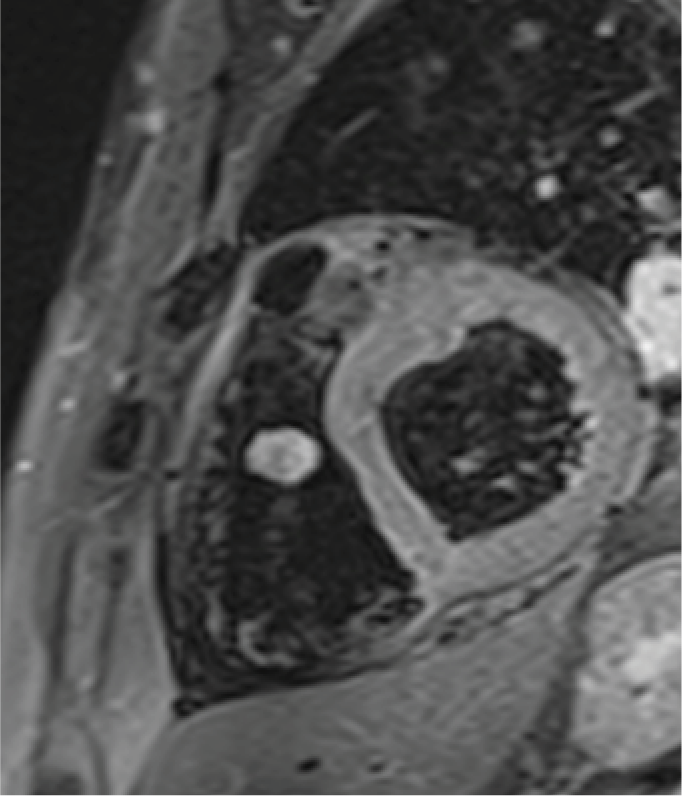

Resonancia magnética cardiaca

La resonancia magnética cardiaca es un una técnica de imagen que permite estudiar detalladamente y en una sola exploración la función y la estructura del corazón. Este auxiliar diagnóstico utiliza un potente campo magnético, sin radiación, para generar imágenes detalladas de las estructuras del corazón.

La resonancia magnética esta indicada en la evaluación de las cardiopatías congénitas tanto en el niño como en el adulto, en la evaluación de la perfusión miocárdica (resonancia cardiaca con gadolinio), de la función cardiaca, de las enfermedades del músculo cardiaco (miocardiopatías), tumores del corazón y del tejido que rodea al corazón (pericardio).